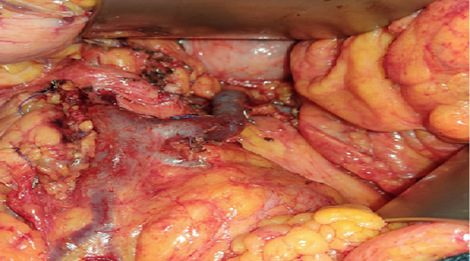

Figure 1: Distal Pancreatectomy with Spleen Preservation.

A 50-year-old woman, with no significant past medical history, presented with vague abdominal pain lasting for 6 months. Abdominal ultrasound revealed a unilocular cystic lesion with thick walls. Contrast-enhanced CT scan demonstrated a well-defined hypodense lesion in the pancreatic tail, measuring 15×18 mm, with peripheral calcifications. The patient underwent a distal pancreatectomy with spleen preservation using splenic vessel conservation. The postoperative course was uneventful. Final histopathology confirmed a mucinous cystic neoplasm without invasive features.